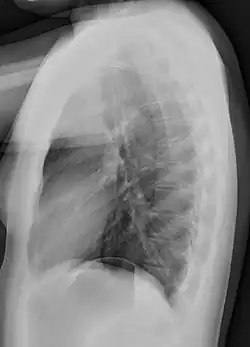

Normal lateral chest radiograph.